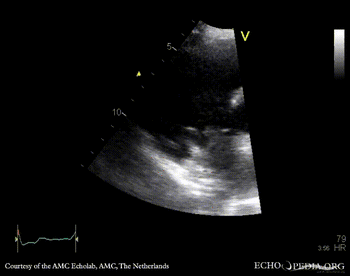

Endocarditis of pacemaker lead

PSAX: mobile structure on pacemaker lead A4CH: mobile structure on pacemaker lead